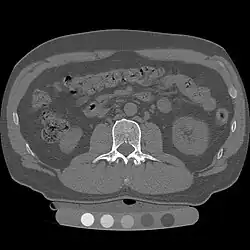

Quantitative computed tomography (QCT) is a medical technique that measures bone mineral density (BMD) using a standard X-ray computed tomography (CT) scanner with a calibration standard to convert Hounsfield units (HU) of the CT image to bone mineral density values.[1] Quantitative CT scans are primarily used to evaluate bone mineral density at the lumbar spine and hip.

In general, solid phantoms placed in a pad under the patient during CT image acquisition are used for calibration. These phantoms contain materials that represent a number of different equivalent bone mineral densities. Usually either calcium hydroxyapatite (CaHAP) or potassium phosphate (K2HPO4) are used as the reference standard.[2]

QCT scan protocols are low-dose and can limit the amount of radiation exposure to between 200-400μSv for a spine exam[6] This is comparable to a set of mammograms and typically substantially less than a standard CT exam. Using other non-IV contrast abdominal or pelvic scans such as a Virtual Colonography studies, the QCT exam can be performed without requiring any further image acquisition or consequent radiation dose to the patient.[7]

Dual use of CT images

Several studies have shown that bone density may be measured by QCT using CT images that were ordered for other purposes. Using pre-existing images, including CT colonography exams,[14] QCT allows for bone density screening without submitting the patient to any additional radiation exposure. The feasibility of using routine abdominal contrast-enhanced CT scans for the evaluation of bone density by QCT has also been demonstrated.[15]